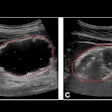

Example of a real mass (noncalcification lesion) converted to appear for the four detector types of the study at the same dose. Top left: aSe; top right: CsI; bottom left: CR NIP; bottom right: CR PIP.From April 2011 to December 2012, all available mammograms with a malignancy and a random selection of biopsy-proven benign lesions and normals were collected from systems by Hologic to create a database. An expert radiologist, who did not participate in the study, marked a region of interest (ROI) around the cancers and benign lesions in the database and classified their appearance (mass, distortion, focal asymmetry, calcification clusters) and conspicuity (very subtle, subtle, or obvious) in each view.